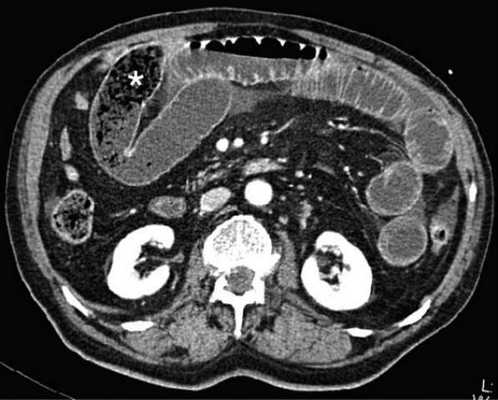

(а) При КТ с контрастированием в аксиальной проекции выявлена транспозиция верхней брыжеечной артерии (указатель) и вены (стрелка).

(б, в) На более низких уровнях при КТ в аксиальной проекции выявлен симптом «водоворота» (стрелка), представляющий собой перекручивание верхней брыжеечной вены и ее ветвей, брыжеечного жира и петель кишки вокруг верхней брыжеечной артерии по часовой стрелке.

Ультрасонография (УС) информативна при патологическом перекручивании верхних брыжеечных артерии и вены (симптом «водоворота»), выявляемом при цветном допплеровском картировании. Однако зависимость от мастерства исследователя, а также газ в тонкой кишке, мешающий исследованию верхних брыжеечных сосудов, часто ограничивают диагностическую пользу. КТ стала важным методом визуализационной диагностики, особенно при завороте тонкой кишки у взрослых. Как и при УС, характерным признаком при КТ служит симптом «водоворота», который возникает в результате перекручивания верхней брыжеечной вены и ее ветвей, брыжеечного жира, кишки и ветвей верхней брыжеечной артерии вокруг самой верхней брыжеечной артерии, чаще по часовой стрелке.